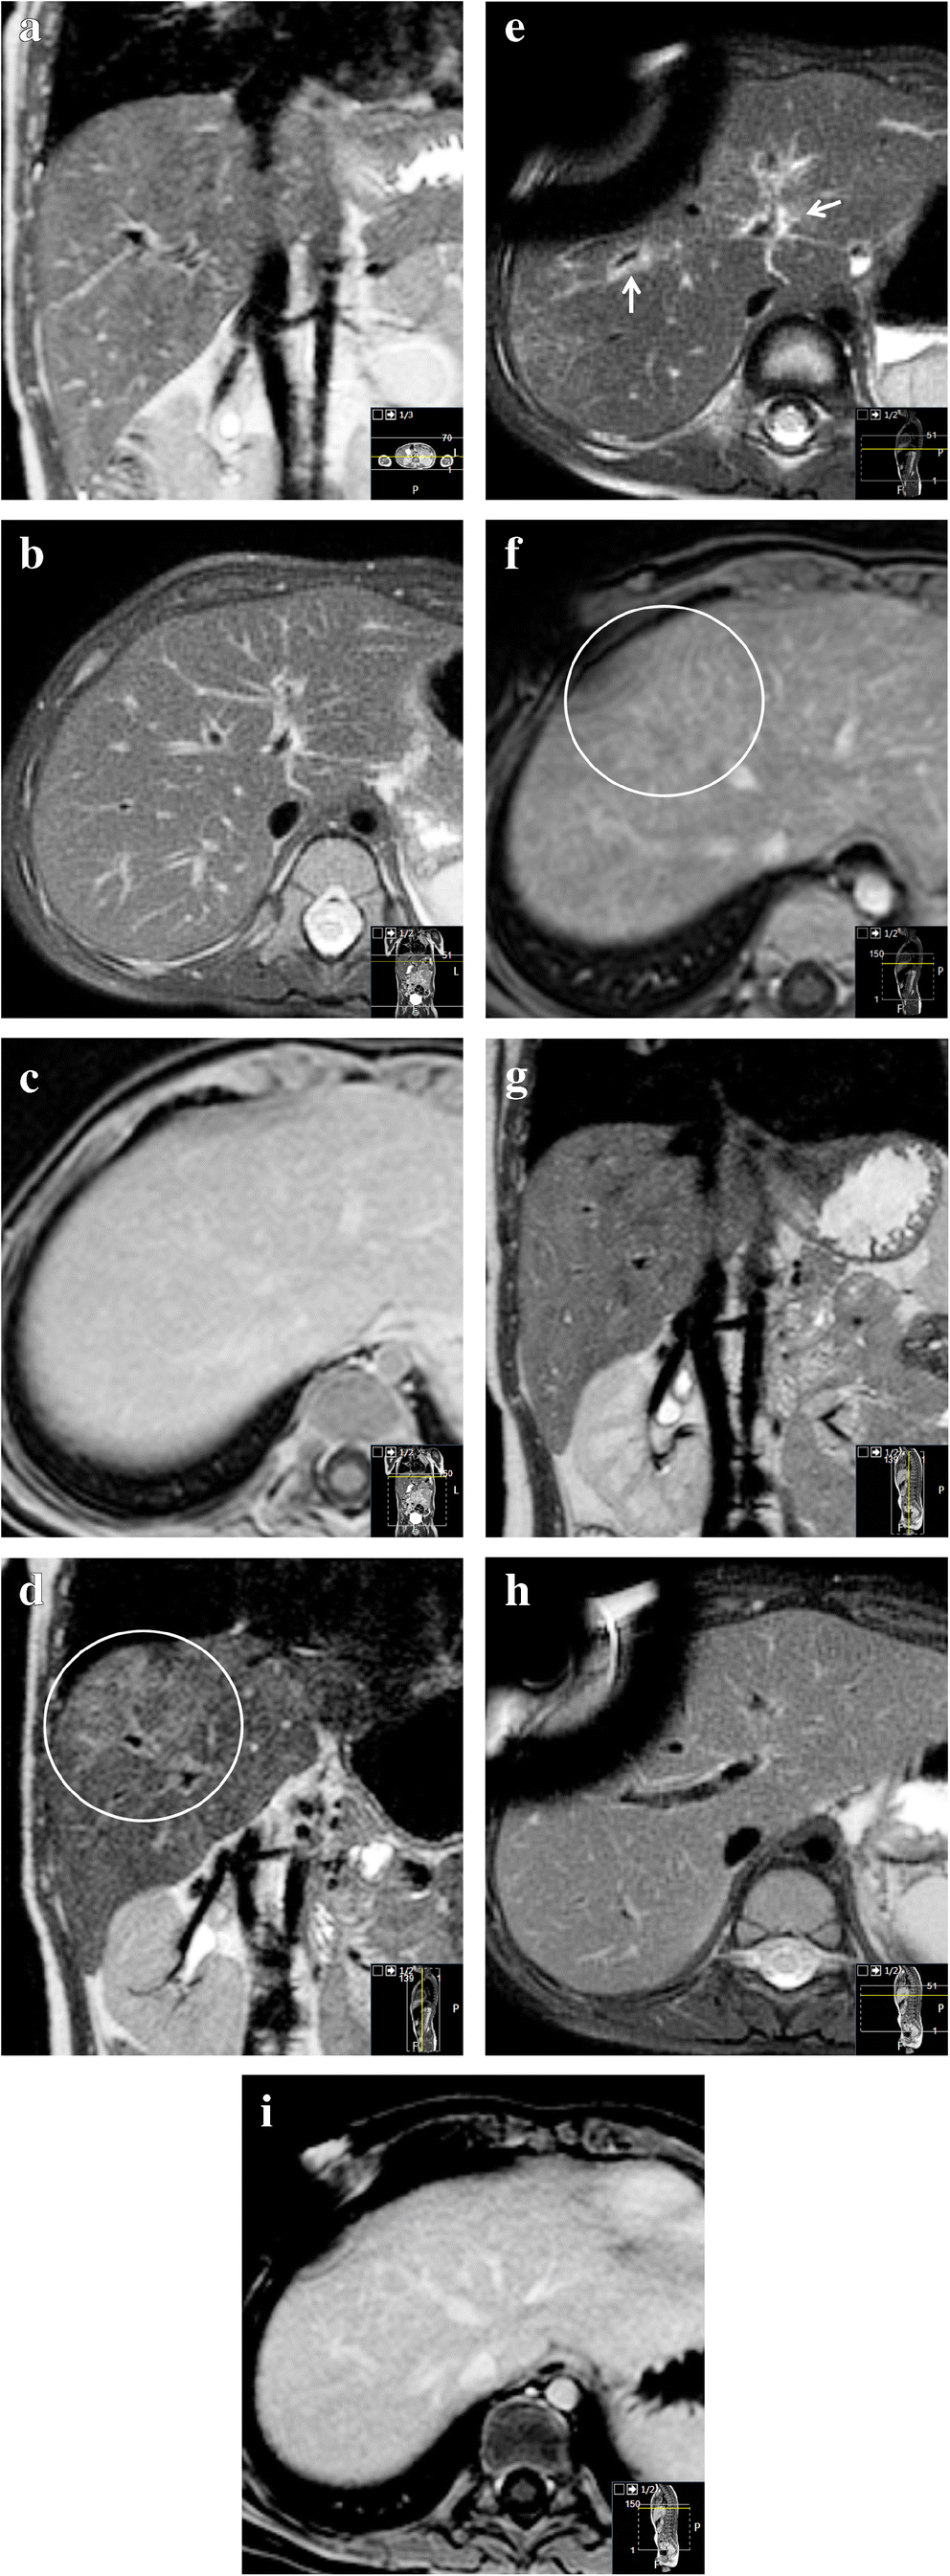

Magnetic resonance imaging

As with CT, available literature of MRI features of sinusoidal obstruction syndrome focuses on adults. We found no papers describing pediatric cases. Similar to findings on US and CT, ascites, hepatomegaly, periportal edema, and gallbladder wall thickening are general features that can be recognized on MRI [14]. From our experience, incidental transient patchy hepatic T2 heterogeneities with reticular enhancement with or without ascites can be encountered on follow-up MRI scans during the treatment of nephroblastoma patients on therapy including vincristine and actinomycin D (Fig. 6). Generally, these patients will have no clinical symptoms of sinusoidal obstruction syndrome, although thrombocytopenia often seems to coincide with these incidental MRI abnormalities. As shown by Jagt et al. [8], almost half of nephroblastoma patients pretreated with regimens containing actinomycin D have histological proof of sinusoidal obstruction syndrome on liver biopsies during tumor resection, whereas clinical manifestations of sinusoidal obstruction syndrome were present in a minority of these patients. Therefore, we hypothesize that these hepatic abnormalities on MRI could be manifestations of subclinical sinusoidal obstruction syndrome. From our experience, these subclinical liver MRI abnormalities usually resolve spontaneously on subsequent follow-up MRI (Fig. 6).

Fig. 6

Transient chemotherapy-related hepatic abnormalities on magnetic resonance imaging (MRI) for possible subclinical sinusoidal obstruction syndrome. A 2-year-old boy with Beckwith-Wiedemann syndrome with stage-I high-risk nephroblastoma was treated according to the SIOP (Société Internationale d’Oncologie Pédiatrique/International Society of Paediatric Oncology) 2001 protocol with actinomycin D, vincristine and doxorubicin. No liver abnormalities were present on the MRI before treatment. a–c Pretreatment coronal three-dimensional T2-weighted turbo spin echo MRI (a) (repetition time [TR]/echo time [TE] 447/90 ms), transverse T2-weighted fat-saturated multivane xd MRI (b) (TR/TE 2,666/67.1 ms) and gadolinium-enhanced transverse T1-weighted high-resolution isotropic volume examination MRI (c) (TR/TE 5.46/2.68 ms) show no abnormalities of the liver. d–f Eight months later, during the seventh month of postoperative treatment, identical MRI sequences at the same anatomical locations show hepatic abnormalities. The images show patchy T2 hyperintensities (circle in d), periportal edema (arrows) and a reticular enhancement pattern (circle in f). There was no liver enlargement, no gallbladder edema and no relevant ascites. Clinically, there were no signs or symptoms of sinusoidal obstruction syndrome. Liver enzymes were not tested at that time. Platelet count was low (53×109/L (normal 150–450×109/L); in combination with leukopenia, this was considered to be caused by the chemotherapy. The differential is a subclinical sinusoidal obstruction syndrome [8]. g–i Follow-up MRI another 7 months, again with identical sequences, planes and anatomical location to (a), (b) and (c), show that the abnormalities spontaneously resolved while the patient was still on treatment. Susceptibility artefacts originate from the permanent intravenous catheter